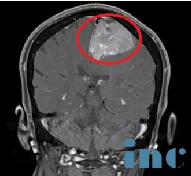

脑膜瘤可能发生在有硬脑膜的任何地方,但常见的部位是大脑半球,它是一种在女性中比男性更常见的脑瘤...